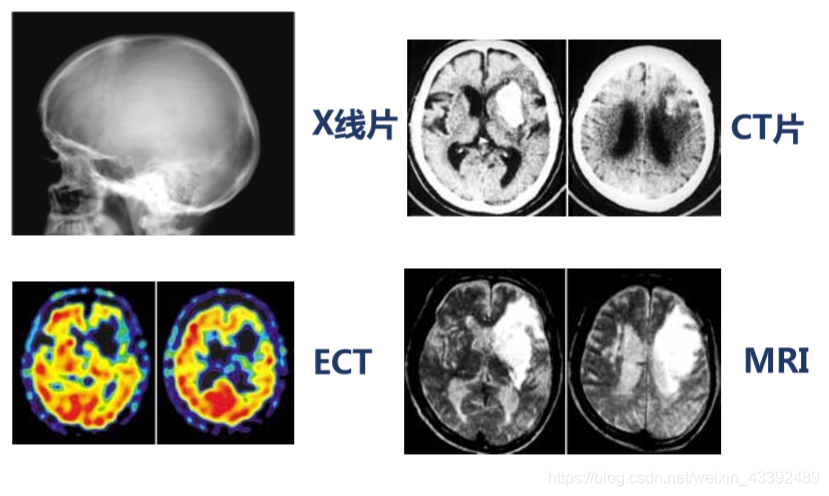

医学应用:通过CT及核磁共振、超声波、X射线成 像的分析等,可提供医学诊断依据。

CT (Computed Tomography) 计算机断层摄影术